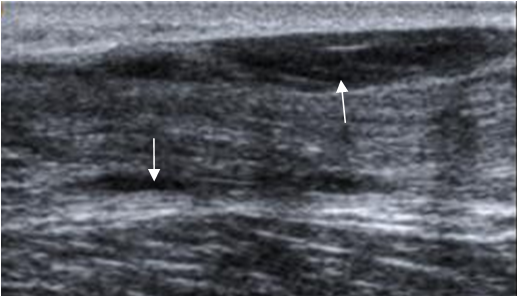

Fig 72. Tenosinovitis del aquiles.

Ecografía longitudinal. Liquido rodeando el tendón de aquiles, por tenosinovitis.